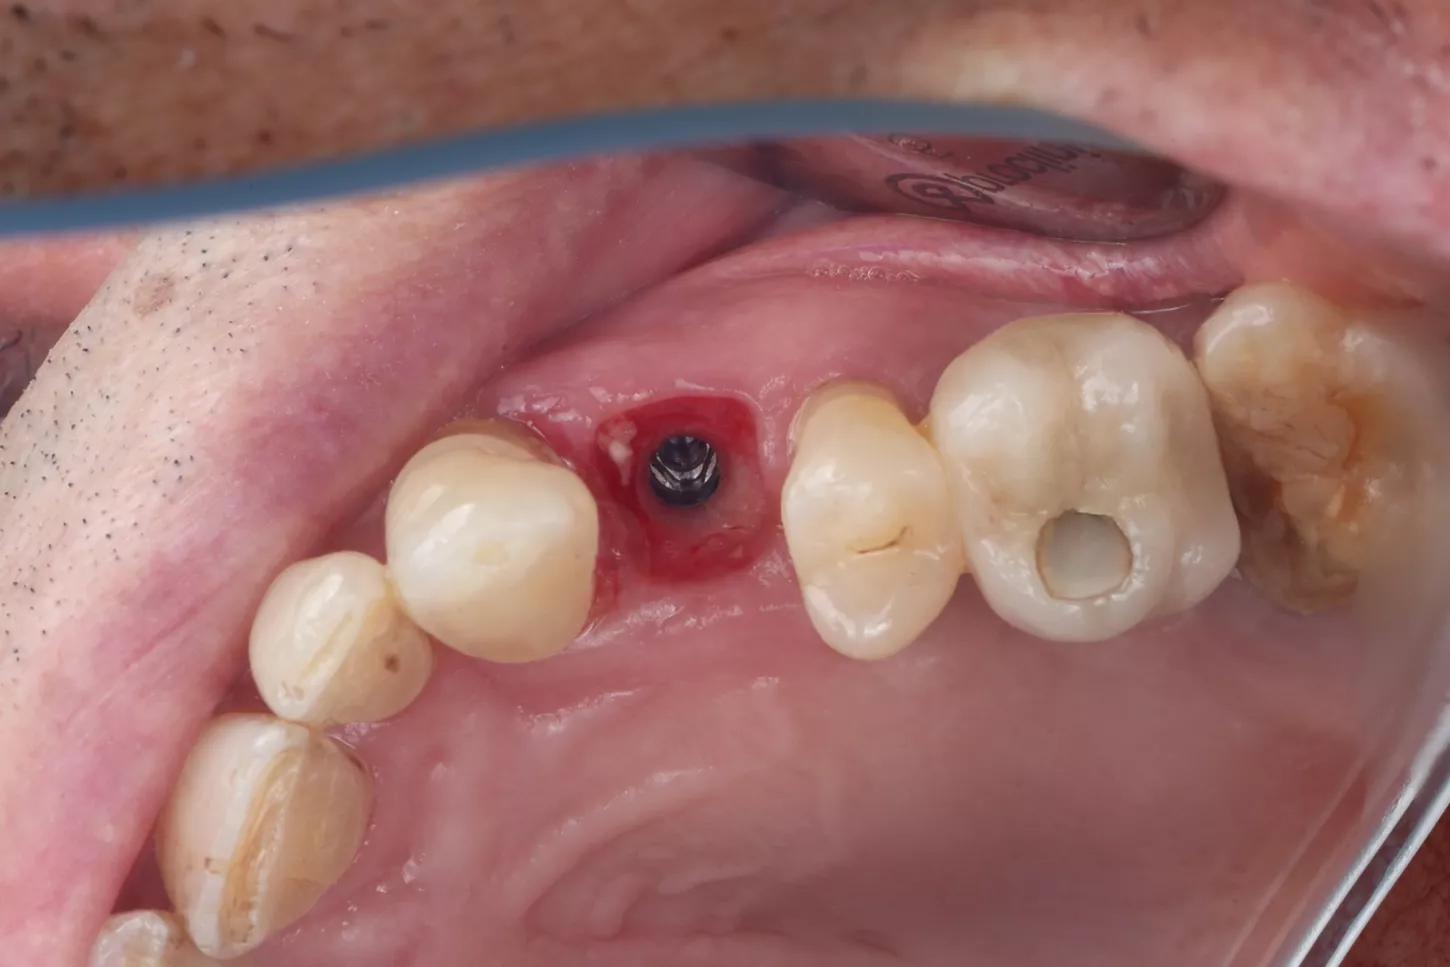

After healing, implant placement was performed using a tooth-supported surgical guide under local anaesthesia. A limited buccal flap allowed visual control and creation of a pouch for a connective tissue graft. Osteotomy was completed with the Integral surgery kit, and a 3.4×12 mm Axiom® X3 implant (XT34120) was placed under fully guided conditions with a Healfit® SH (OPSHSC23) healing abutment connected. A palatal connective tissue graft was positioned buccally to enhance soft-tissue thickness. The flap was sutured with 5-0 interrupted and mattress sutures. Postoperative care mirrored Phase I, with uneventful healing observed (Fig 4 a&b).

4a. 4b. Lateral view showing Healfit® SH healing screw connected to the implant and occlusal view of sutures for tension-free closure.

4a

4b